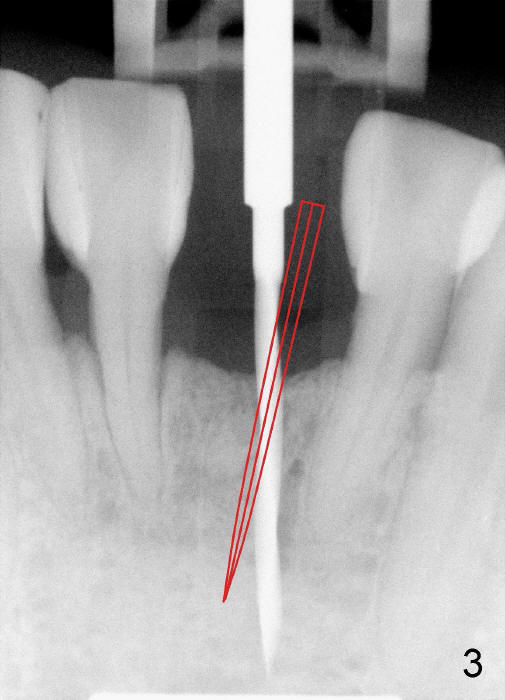

A 3x17 mm one piece implant is planned. Osteotomy is created by a 1.5 mm pilot drill at the depth of 14 mm without incision (Fig.2); it is close to a neighboring incisor. The trajectory of the osteotomy is intended to be changed (Fig.3 red) without success (white, 17 mm deep). With measurement and calculation, the 3x17 mm implant is not expected to touch the root of the adjoining tooth. In fact it is fine with insertion torque between 50-60 Ncm (Fig.4). Without incision, the papillae appear to form immediately following implantation (Fig.5). With adjustment of the abutment (Fig.6), an immediate provisional is fabricated (Fig.7).

To place the implant correctly, the preop PA should be studied carefully to find the divergence of the roots of the neighboring teeth (Fig.1). The depth of the initial osteotomy should be shorter, for example, 11 mm instead of 14 mm. Once the trajectory is found to be corrected, an incision should be made; the osteotomy is to be overcorrected with Lindermann bur (Fig.8 black); the whole osteotomy is changed with proper angulation (Fig.9 arrows).

Fig.10,11 show 7 day follow up. The permanent crown is seated 4.5 months postop (Fig.12). Minimal bone resorption occurs at the crest 4 months postop (Fig.13), which is most likely associated with conservative approach (flapless). The patient returns for follow up 2.5 months post cementation (Fig.14,15). The implant remains in the bone 4 years post cementation (Fig.16 CT coronal section; lingual thread exposure, corresponding to preop defect in Fig.1). There is mild coronal bone resorption 5 years 4 months post cementation (Fig.17).